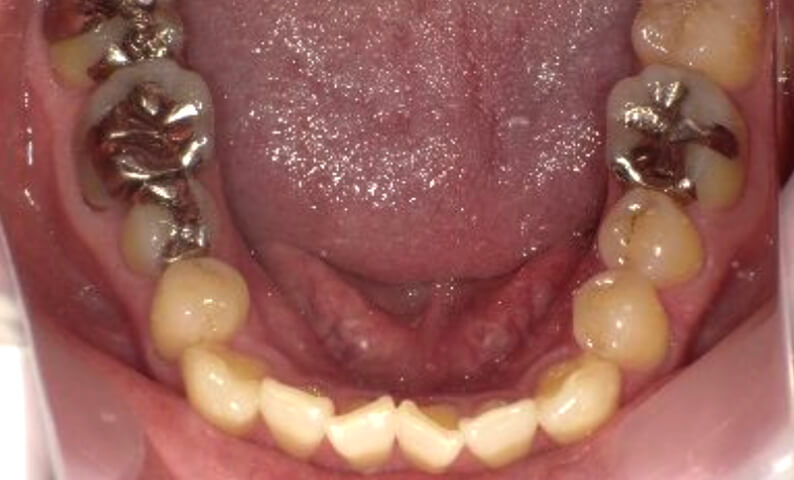

症例_003 下顎だけの部分矯正

治療期間:10ヶ月金額:24万円+税女性前歯のガタガタ下の前歯だけ上顎は補綴治療中

| Before | After |

|---|---|

|